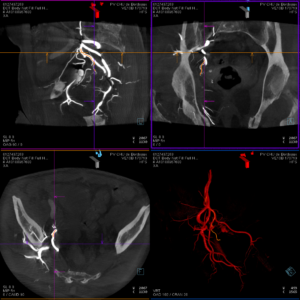

Les artères prostatiques connaissent de nombreuses variantes d'où la difficulté potentielle du geste. Il peut exister une à deux artères par côté (1,4 en moyenne). Le diamètre des artères prostatiques est d'environ 1 mm. L'origine de ces artères est très variable en fonction des patients ce qui rend ce geste difficile. Une acquisition 3D permet de repérer la ou les artères prostatiques et de les cathétériser à l'aide d'une superposition entre l'image 3D et l'image radiographique.

Une fois placé dans l'artère prostatique, on s'assure par des acquisitions 3D de l'absence d'anastomose et donc l'absence de risque d'embolisation hors cible. Puis, on injecte des microparticules (diamètre moyen de 300 à 500 microns) jusqu'à arrêt complet du flux. Ces microparticules peuvent être remplacées ou complétées par l'injection d'un agent liquide (Onyx® ou Glubran®) en fonction de la configuration vasculaire qui ont l'avantage de réaliser une occlusion complète et définitive du vaisseau cible avec une meilleure visualisation à l'injection.